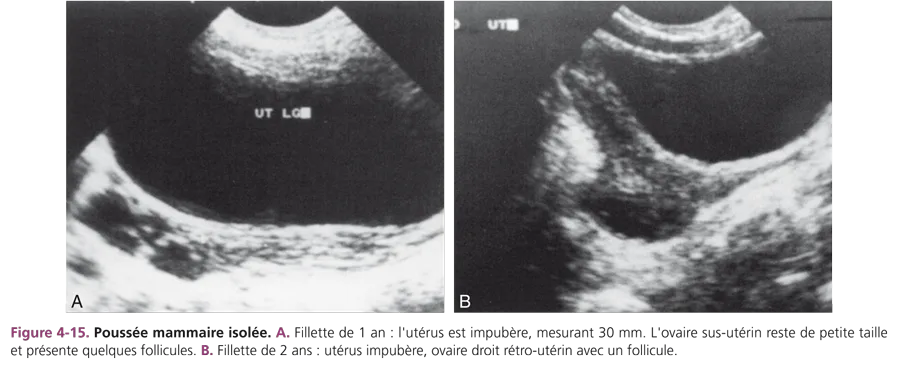

Développement mammaire isolé ou prémature thélarche Il survient souvent chez les petites filles de 6 mois à 3 ans. L’examen échographique montre un utérus et des ovaires d’aspect impubère, normal pour l’âge. Les ovaires de petite taille peuvent présenter des follicules (fig. 4-15). Le bilan hormonal est normal.

Une surveillance clinique reste indispensable, contrôlant la régression spontanée du symptôme. L’évolution vers une puberté précoce vraie se voit surtout chez la fillette de 4 à 7 ans.

L’hypothèse d’un excès de réceptivité aux oestrogènes des organes cibles est évoquée. Le même mécanisme expliquerait les métrorragies isolées.